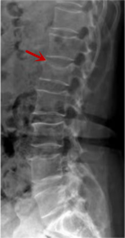

腰椎X線片作為最基礎(chǔ)的影像檢查手段,利于X線穿透人體組織后成像,以其快捷、直觀、價(jià)格低廉的特點(diǎn),X線檢查主要包括腰椎正側(cè)位、雙斜位以及過伸過屈位。主要用于觀察腰椎骨骼的情況,如椎體是否有骨折、骨質(zhì)增生程度、生理曲度的變化、椎體移位的情況等。然而,X線檢查也有它的局限性,無法判斷是骨折的新舊,對于椎體內(nèi)部結(jié)構(gòu)和周圍肌肉韌帶組織(如脊髓神經(jīng)、椎間盤、韌帶等)的顯示不佳,另外X線作為有輻射檢查,孕婦及嬰幼兒謹(jǐn)慎選擇。

箭頭提示腰1椎骨折

箭頭提示腰3椎體滑脫